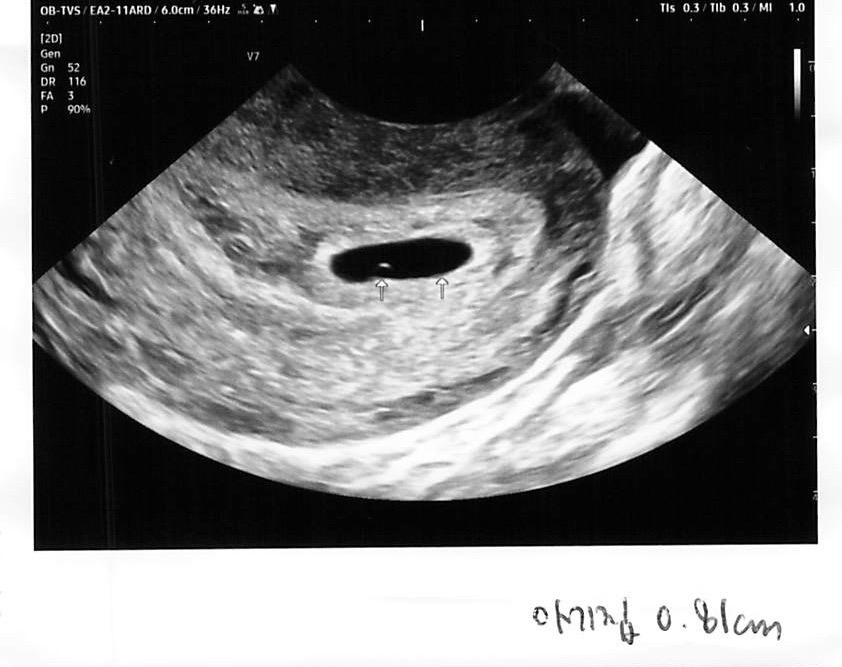

이틀전에 산부인과 가서 보고왔어요! 쪼끄만 점이 난황이래요ㅋㅋ 너무 귀여워요 생애 첫 임신이라 아무것도 모르겠는데 이정도면 크기 괜찮은걸까요? 빨리 심장소리 들어보고 싶어요!